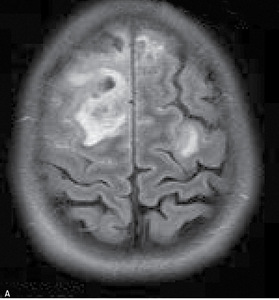

Rutynowa tomografia komputerowa bez środka cieniującego w 20% przypadkach pozwala stwierdzić hiperintensywne skrzepliny w rzucie zatok lub żył mózgowia (dense clot sign) (ryc. 1). W przypadku zakrzepicy żył korowych niekiedy widoczny jest tzw. objaw struny (czyli linijna, hiperintensywna zmiana odpowiadająca zakrzepowi w świetle naczynia żylnego). Pośrednim objawem CVT są cechy obrzęku mózgu (np. spłycenie bruzd, zwężenie układu komorowego, obserwowano w 20-50% przypadków). Charakterystyczna dla udaru żylnego jest lokalizacja ogniska naczyniopochodnego (zarówno niedokrwiennego, jak i krwotocznego) nie odpowiadająca zakresowi unaczynienia tętnic mózgowych, oraz liczne izolowane ogniska położone podkorowo z zaoszczędzeniem kory mózgu.11 Zakrzepica zatoki prostej zwykle upośledza drenaż żylny na dużym odcinku, co skutkuje zmianami zlokalizowanymi w rejonie parasagitalnym (ryc. 2A, B). Zakrzepica żyły zespalającej dolnej (żyła Labbego) prowadzi do zmian w płacie skroniowym. Zakrzepica żył głębokich mózgu powoduje jednostronne lub obustronne zmiany we wzgórzach, jądrach podstawy i torebce wewnętrznej.11W około 30-40% przypadków CVT towarzyszą ogniska krwotoczne. Zgodnie ze stanowiskiem ekspertów American Heart Association (AHA) i American Stroke Association (ASA) w przypadkach krwotoków płatowych o niejasnej etiologii i (lub) lokalizacji nieodpowiadajęcej zakresowi unaczynienia tętniczego, należy brać pod uwagę możliwość CVT.4,11